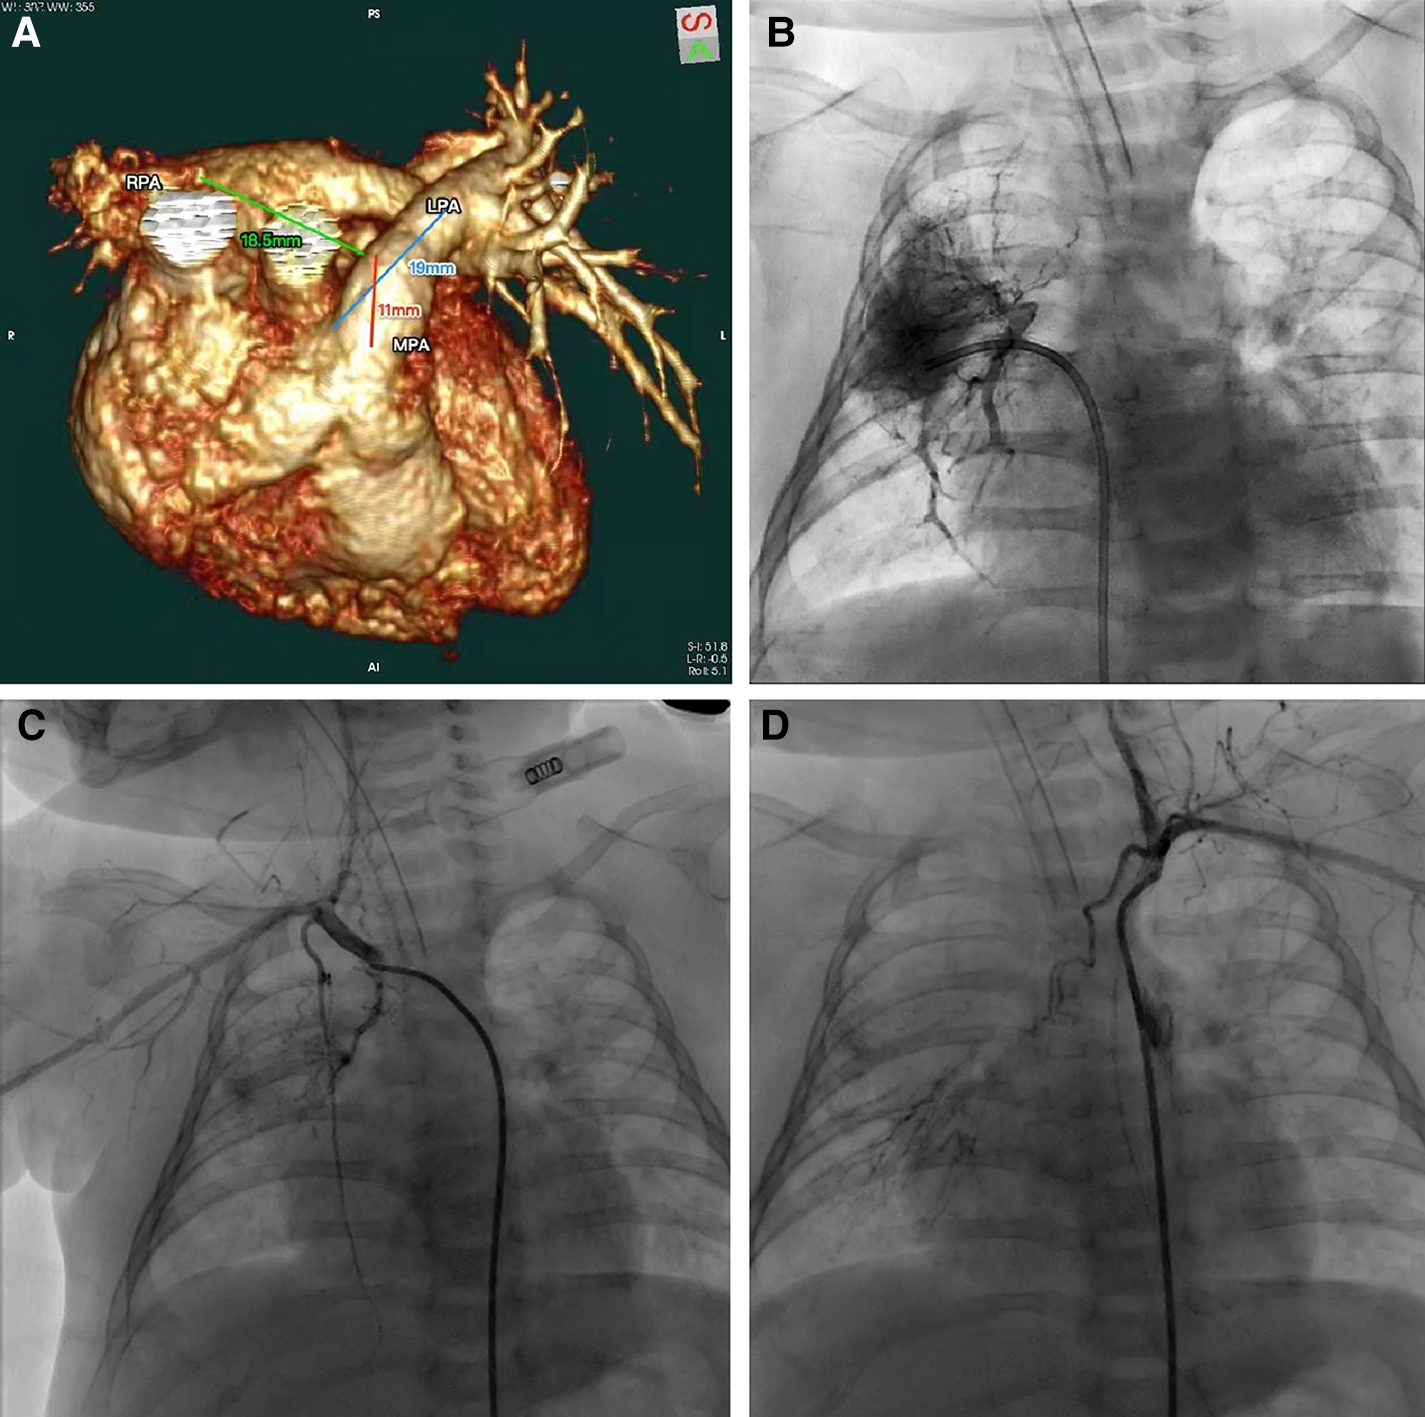

Our patient was a 2-month-old girl first presented with convulsion due to pneumonia at 4 days old. No obvious cardiac abnormality was discovered upon initial physical examination. Echocardiography at the time suggested the absence of RPA, a patent ductus arteriosus, a patent foramen ovale and pulmonary hypertension. She was then transferred to our institution for further treatments. Preoperative computer tomography angiography (CTA) and three-dimensional reconstruction revealed the absence of intrapericardial RPA, of which the diameter of distal RPA at hilus is normal. The diameters of MPA and left pulmonary artery (LPA) was 8.3 mm and 5.1 mm respectively (with z-scores of −1.25 and −0.83 respectively). The gap between the RPA at the hilum and MPA was estimated to be 18.5 mm (Figure 1A). We further performed cardiac catheterization for diagnostic purposes, which further revealed that blood supply of upper RPA comes from right subclavian artery, while inferior RPA was supplied by left subclavian artery through long collateral vessels (Figures 1B,D). Systolic/diastolic pressure of the ascending aorta (AAo), superior vena cava (SVC), MPA and RPA were 64/29 mmHg, 20/7 mmHg, 51/25 mmHg and 20/10 mmHg respectively.

Figure 1

(A) CTA and three-dimensional reconstruction revealed the absence of intrapericardial right pulmonary artery. (B–D) Cardiac catheterization revealed blood supply of upper right pulmonary artery comes from right subclavian artery and inferior right pulmonary artery was supplied by left subclavian artery.